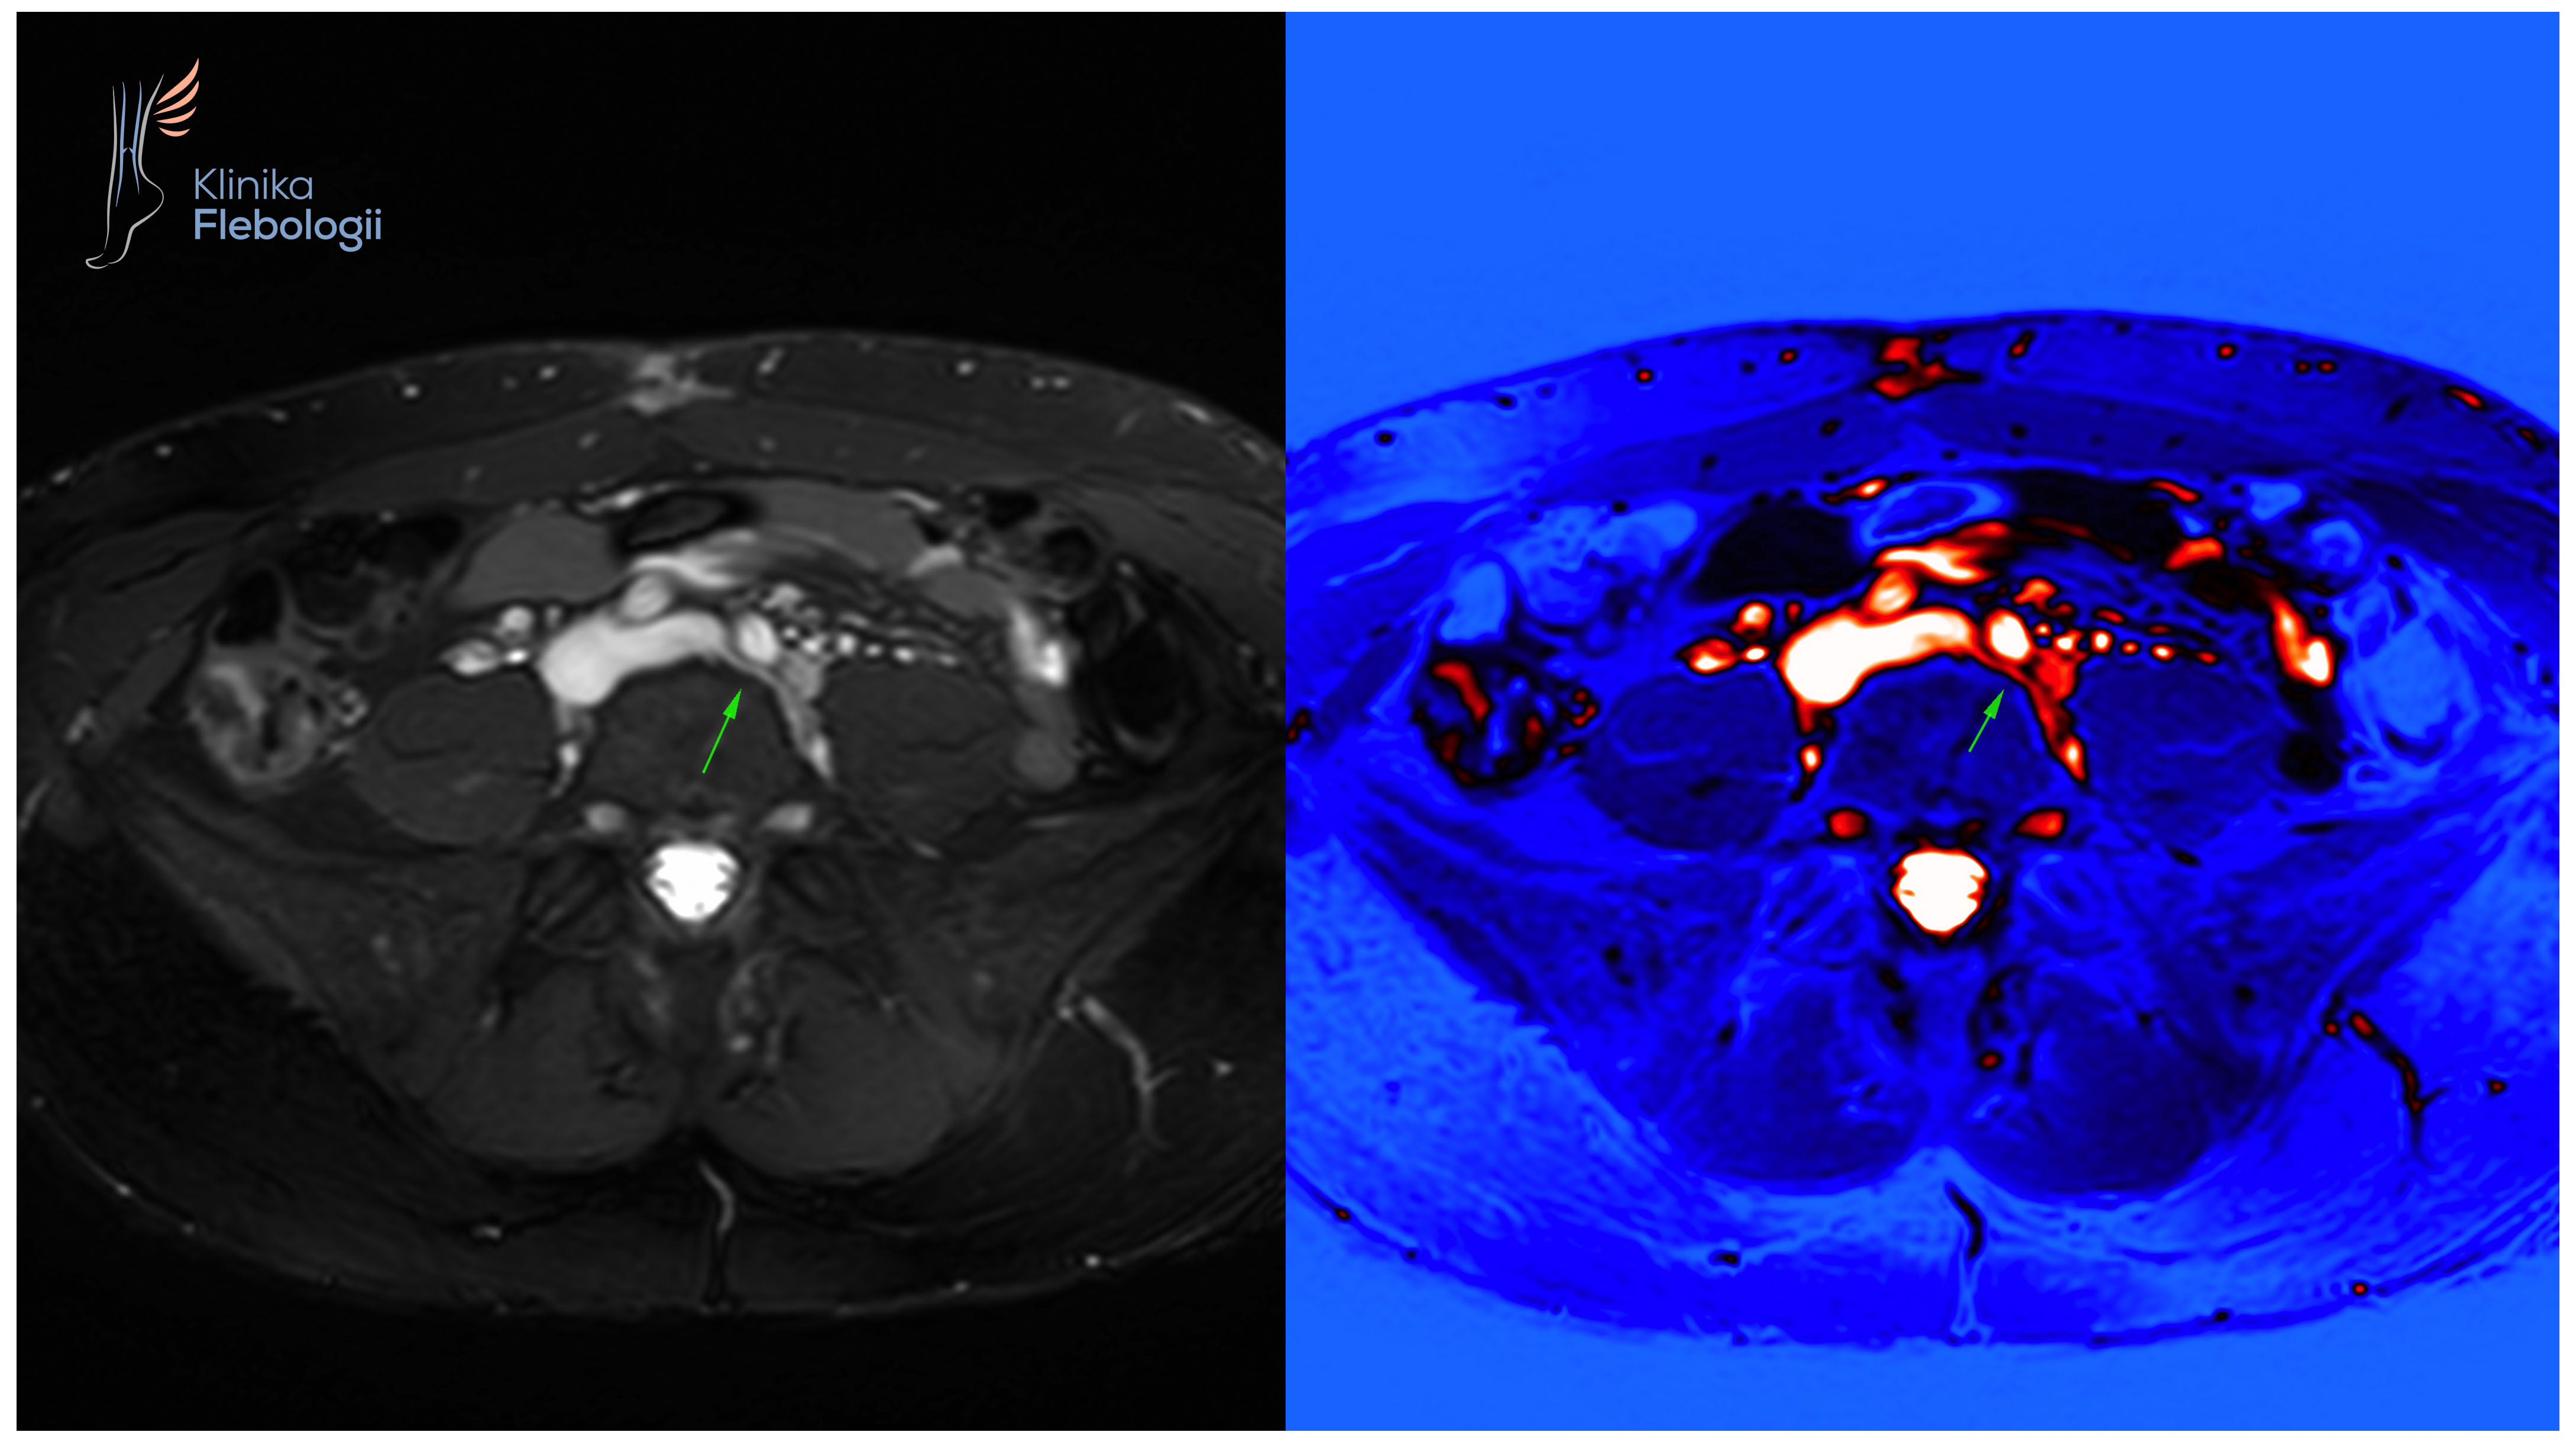

Zespół May-Thurnera. Stentowanie.

Stan po stentowaniu lewego spływu biodrowego w przebiegu zespołu May-Thurnera.

Rzadka postać żylnego zespołu uciskowego na poziomie spływu lewej żyły biodrowej wspólnej.